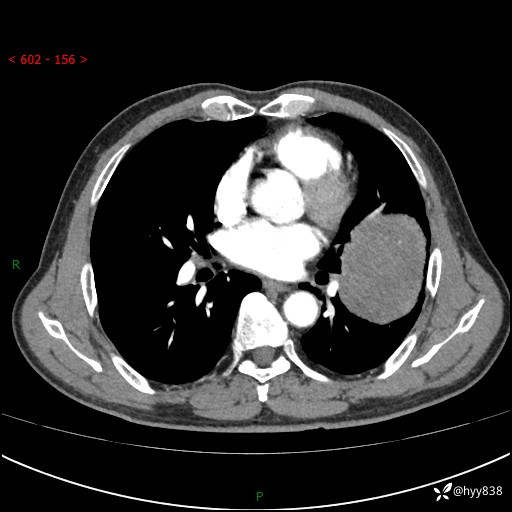

68岁/男,发现左下肺占位5天。如此大的肿块,患者竟然没有症状---结果公布~

【患者信息】:68岁/男

【主诉】:检查发现左下肺占位5天。

【现病史及既往史】:患者于4天前外院行“经尿道钬激光碎石术”,住院期间胸部CT检查发现左下肺肿块,患者平素无明显咳嗽咳痰,无心慌、胸闷、胸痛、呼吸困难、低热、盗汗,无头痛、头晕,无腹痛、腹胀等不适,现患者为求进一步治疗,遂来我院就诊,以“左下肺肿块”收入我科。 患者自起病以来,精神可,睡眠可,饮食可,大小便正常,体重无明显改变。

【检查】:胸部CT增强扫描